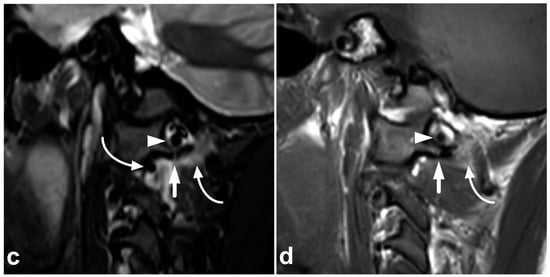

4.1. Occipitocervical and Atlantoaxial Ligaments

The craniocervical and atlantoaxial joints are mobile structures allowing flexion–extension movement and rotation of the head. The joints’ biomechanics and the importance of different stabilizing structures are not yet completely understood. The joint capsules, the alar ligaments, and the transverse ligaments are crucial to stability [33,38,39]. The role of the tectorial membrane is more controversial, but it might also be of importance in preventing overextension [33,40]. Injury to the stabilizing joints or ligaments may lead to instability. Isolated soft tissue injuries and avulsion fractures without complete joint dissociation (Figure 4) may occur. All the joints and ligaments mentioned above are visible on MRI. A higher field strength and dedicated proton density- and T2-weighted sequences with a smaller field of view may help to delineate these small structures better [41]. Figure 8 demonstrates a case with an upper cervical spine ligament injury.

Figure 8.

(a) Axial T2-weighted. (b) Coronal PD-weighted. (c) Right-sided off-midline sagittal PD-weighted. (d) Sagittal PD-weighted. (e) Sagittal STIR. A 12-year-old male, football injury. The right alar ligament (white arrows) is torn. The right side of the transversal ligament is thickened and heterogenous, suggesting a partial distension injury (white arrowheads). The left alar ligament (black arrows) and the central and left-sided portions of the transversal ligament (black arrowheads) are intact. The tectorial membrane is unharmed (curved black arrows), but the apical ligament of the dens is poorly visible, probably torn (curved white arrow). Apparent asymmetry of the lateral atlantodental intervals is seen, but there are no signs of occipitocervical or atlantoaxial joint capsule disruption.